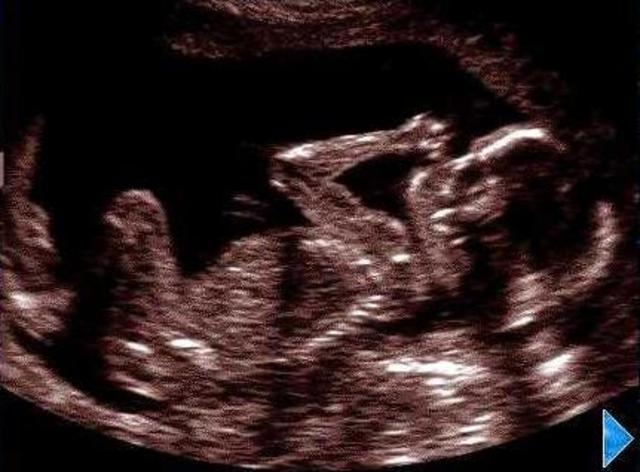

• Month 8

Month 8

Baby is gaining half a pound per week and is turned head down in preperation for birth. Baby weighs 2.5-3 pounds and is 14-16 inches long. Mother has discomfort from enlarged abdomen and is 18-20 pounds larger.

• Month 9

Month 9

Baby has less room for movement. Baby weighs 5-6 lbs and is 17-18 inches long. Mother feels lightening as fetus drops into pelvis and feels false labor pains.